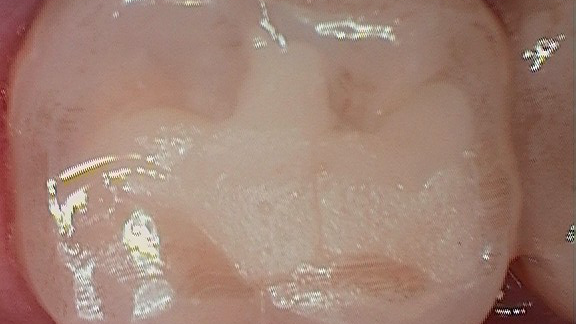

Figure 3 shows the final restoration immediately after placement. Figure 4 shows the final restoration of an initial caries lesion on the buccal. The clinician anticipated maturation of the glass-hybrid in choosing a lighter shade of A2, which initially appeared much too light. A slightly darker shade may have been more appropriate.

Figure 5 is a 36-month follow-up bitewing radiograph demonstrating excellent support of the significantly undermined enamel and deposition of secondary dentin in the mesial pulp horns. Figures 6 and 7 show the occlusal and facial restorations respectively after 18 months. Notice the improvement in shade.